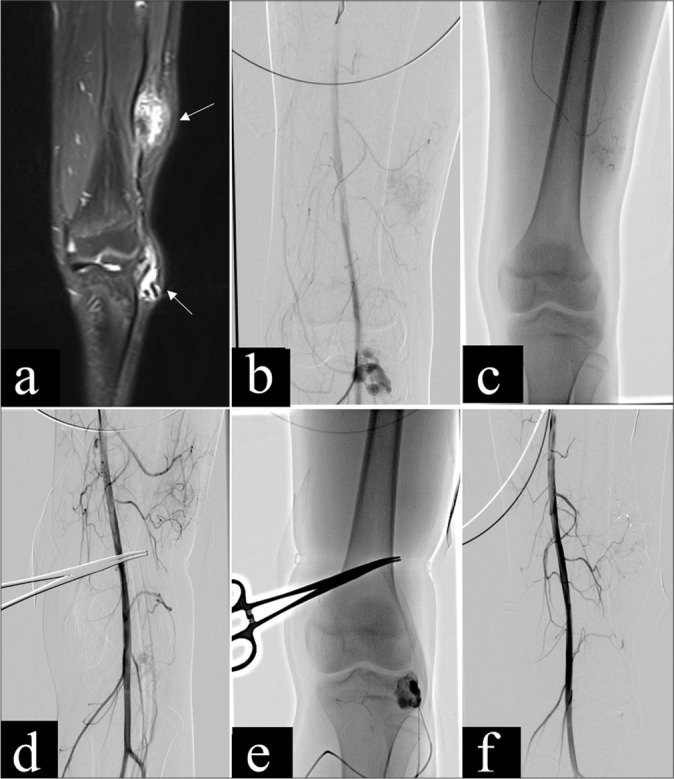

Objectives: Congenital arteriovenous malformations (AVMs) are characterized by abnormal connections between arteries and veins, often presenting challenges in treatment due to their complex vascular structure. Endovascular therapies, including embolization techniques, have become integral in managing AVMs, yet optimal treatment strategies remain under investigation. This retrospective study aimed to evaluate the safety and efficacy of percutaneous glue embolization of n-butyl cyanoacrylate (nBCA) combined with arterial embolization in treating extracranial AVMs.

Material and methods: This retrospective study included 11 patients with extracranial AVMs who underwent percutaneous injection of nBCA glue embolization combined with arterial embolization at our institution between May 2015 and October 2023. Angiographic classification was performed using the Cho-Do vascular imaging system and the Schobinger classification system to categorize the AVMs. Treatment efficacy was assessed based on the percentage of vessel occlusion observed in angiography or imaging studies. The occurrence of major and minor complications was also evaluated.

Results: Eleven patients received 16 treatments, involving a combination of arterial and percutaneous embolization techniques. Five cases achieved complete recovery, while four cases showed significant improvement, resulting in an overall treatment success rate of 81.8%. Favorable outcomes were observed in terms of symptom alleviation and lesion occlusion. Adverse events were minimal, with transient pain and edema being the most common postoperative complaints. Only one case of mild post-operative complication occurred.

Conclusion: Percutaneous glue embolization combined with arterial embolization proves to be a safe and effective treatment modality for extracranial AVMs, with acceptable rates of complications and favorable treatment outcomes.